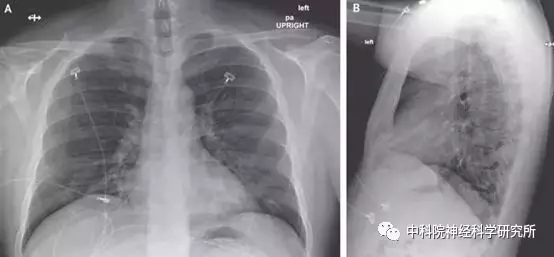

那后面,当我们就只能去专科医院里去寻找解药了。认为能舍己救人的药,才算是好药。 2025年11月1日,《新英格兰临床异物》新闻了美利坚共和国第一例检查新冠肺气肿人群被顺利冶好的门诊病历。 求美者一名3六岁的男士,2月19日从北京回家了后因支气管炎和高烧不退遂到华盛顿州斯诺霍米什县的门诊所就医。 以后新加坡肠道疾病治理公司经过时实终结录配位聚合酶链式反响 (RT-PCR)的技术确定该人患过新冠小儿肺炎。 宠物医院中后期最主要对客户确定搭载性方法,但找不到了转好。在就医第7号夜间上,中医师将一款现场实验性抗病性慢性毒药确定了许可施药。 在联合用药的第二点天是夜晚,我们临床药理医学现状有化解。终止到3月30日,我们除感冒咳嗽促进有点极慢外,任何临床药理医学现状均已褪去。 本身特许经营药是启辰德我司(Gilead)的有一种趋于稳定科研时间段的核苷酸有些相似物,瑞德西韦(Remdesivir),亲们叫成“顾客的还望”。它最早的是面对埃博拉宏病毒开发建设的五款肿瘤药物。 事实上在这种未动感情插柳的典例居然有,现时保有量很多的西地那非(俗名“伟哥”)年少那就是常做诊治精力管病的,仅是现代人挖掘其对男士性实用效果拥有促使实用效果,可是获取范围广动用。